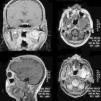

Presentamos a un paciente varón de 32 años, que acudió a las consultas externas del Servicio de Cirugía Oral y Maxilofacial del Hospital POVISA de Vigo por molestias en la articulación temporomandibular izquierda, de meses de evolución. Refería además chasquidos articulares y dolor ocasional no intenso. Su historia clínica no reflejaba ningún antecedente personal de interés. En la exploración física presentaba una asimetría facial, palpándose una tumefacción preauricular izquierda; la exploración intraoral era anodina y no existía limitación de la apertura oral. Se realizó una ortopantomografía, sin mostrar ninguna alteración ósea, por lo que se procedió a realizar una resonancia magnética, tras la administración de gadobutrol intravenoso (fig. 1). Esta mostraba una tumoración con componente sólido y quístico localizada en el espacio masticador izquierdo, con unas medidas de 2,5cm de diámetro transversal, 3,5cm de diámetro anteroposterior y 4,3cm de diámetro craneocaudal, con bordes bien definidos. Tras la administración de contraste, la tumoración presentaba una captación muy escasa e irregular. No se podía descartar ni confirmar la presencia de calcificaciones. La morfología del cóndilo se encontraba respetada, pero se podía evidenciar una destrucción secundaria de la fosa glenoidea, con extensión a la base del cráneo, desplazando el lóbulo temporal. La primera posibilidad diagnóstica a considerar con estos hallazgos fue un sarcoma sinovial, siendo otras posibilidades a valorar una condromatosis sinovial (aunque no parecían evidenciarse calcificaciones) o un granuloma reparativo de células gigantes. Se realizó TC facial (fig. 2) para poder valorar mejor las estructuras óseas y la existencia de calcificaciones; esta mostró una masa sólida redondeada localizada entre el ala externa de la apófisis pterigoides izquierda y el cóndilo del mismo lado, con unas medidas de 3,6×2,9×3,4cm. Tras la administración de contraste intravenoso presentaba un realce heterogéneo. La masa erosionaba la fosa temporal de la articulación, y presentaba un crecimiento intracraneal, ocupando la porción más lateral de la fosa craneal media, con unas medidas de 2,4cm de diámetro transversal y 1,4cm de diámetro craneocaudal. Producía además reacción perióstica, afectando fundamentalmente a la parte más anterior del cuello condilar y a la cara lateral de la rama mandibular. Por tanto, se trataba de una lesión con características radiológicas de agresividad. La primera posibilidad diagnóstica en el diagnóstico diferencial fue la de sarcoma sinovial, sin poder descartar rabdomiosarcoma; otras lesiones agresivas de la articulación parecían menos probables, por las características de captación de contraste, entre ellas la sinovitis villonodular pigmentaria o la condromatosis sinovial (en nuestro caso no se evidenciaban cuerpos libres calcificados).